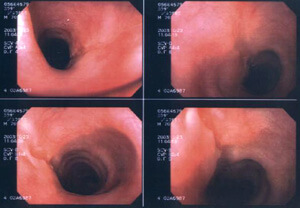

Howply täze döremeleriň içinde gyzylödegiň ragy ýygy duş gelýän (5-7%) görnüşleriň biridir. Ol esasan orta ýaşan we gartaşan erkek adamlarda has köp duş gelýär. Rak köplenç gyzylödegiň ortaky we aşaky böleklerine zeper ýetirýär.

Keseliň döremeginiň esasy sebäplerine, nädogry iýmitlenme – gaty we gyzgyn nahary köp iýmek, alkogol içgileri köp kabul etmek ýaly faktorlar degişlidir.

Keseliň döremek ähtimallygy çilim çekme netijesinde 2-3 esse, alkogol içgileri kabul etmek netijesinde 12 esse artýandyr. Gyzylödegiň rak keseli, onuň nemli bardasynyň aşgarlaryň täsiri netijesinde zeperlenmesinden soň hem köp duş gelýändir. (köp ýyllar geçenine seretmezden).